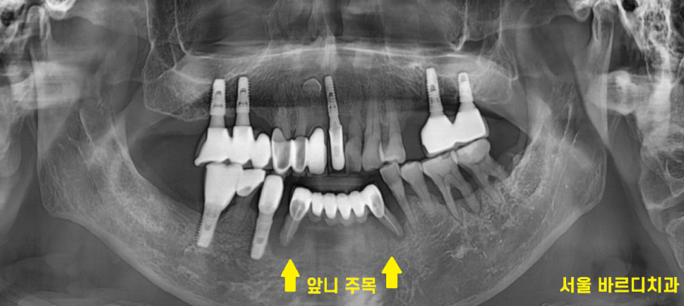

230627

정확한 검사를 시행해 보니

더욱더 확실해졌습니다.

까맣게 된 것이 다 뼈가 녹은 부위입니다.

치아가 손으로 밀어도 흔들린다는 것은

잡고 있는 뼈가 거의 없다는 것

역시나 사진에서 잇몸뼈가 녹아내린 것이 확인

그냥 손으로 잡아 뽑아도 뽑힐 정도였습니다.